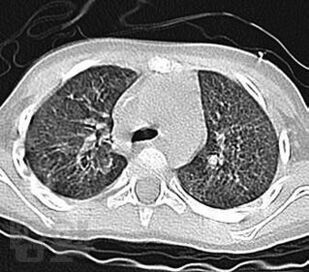

Монография посвящена актуальной теме интерстициальных болезней легких в детском возрасте, многие из которых являются редкими болезнями с тяжелым течением и неблагоприятным прогнозом. В связи с этим своевременная диагности ка и терапия этих болезней необходимы для предотвращения ранней инвалидизации и предотвращения смертности пациентов. Особое внимание уделено гиперсенситивному пневмониту, который в последние годы встречается в педиатрической практике чаще других. В монографии нашли отражение интерстициальные поражения легких при наследственной патологии, диффузных заболеваниях соединительной ткани, системных васкулитах, лекарственных поражениях, болезнях накопления, легочных геморрагиях. Обсуждаются также подходы к проблеме ИБЛ у детей раннего возраста.

В книге обобщены современные данные литературы о различных клинических вариантах ИБЛ, со многими из которых авторам непосредственно пришлось иметь дело в практической деятельности на протяжении не одного десятка лет, и, которые представляют наибольший интерес и важность с точки зрения встречаемости и клинической значимости в детском возрасте.